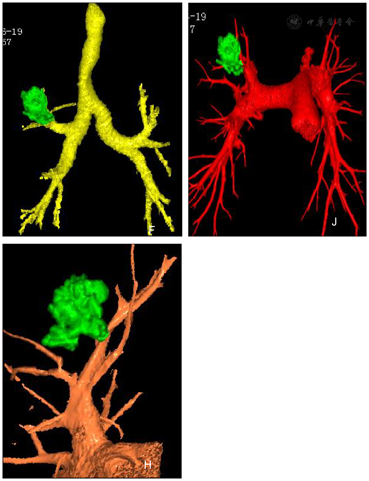

男性,70岁,咳嗽、咳痰1个月余,图ACT平扫右肺上叶前段可见1.5cm×1.7cm×2.9cm结节,边缘可见浅分叶征,上叶支气管开口处可见杯口征,平扫CT值43HU。增强扫描动脉期病灶实质部分强化,CT值62HU。静脉期65HU,延迟期68HU。图B示肿瘤内可见肿瘤微血管CT成像征。通过碘图分析及癌灶碘参数测量:动脉期IC:1.1mg/ml,NIC;0.08。图C示静脉期IC1.2mg/ml,NIC:0.26,延迟期IC0.9 mg/ml NIC0.31。静脉期碘图(0.34)诊断肺癌(腺癌)的阈值。纵膈隆突前、隆突下增大淋巴结碘图AEF值0.64~0.74,考虑淋巴结转移瘤,隆突左侧淋巴结0.58,考虑非转移性淋巴结。VR图像示:绿色结节为肿瘤,好像一只怪兽的狰狞面目。深红色为肺动脉,淡红色为肺静脉,螺旋状为支气管动脉夹杂其间。周围可见血管集束征,表面可见小结节堆积征。图D示病灶呈分叶状位于右肺上叶支气管开口处。

双源CT容积再现技术VR在肺癌术前模拟切除术的应用,常规螺旋CT后处理技术中MPR等也可进行三维重建,但其在肺内气管、支气管、血管、肺组织的三维重建等成像效果较差,无法精确描述结节病灶的形态及其与周围组织关系,影像诊断医师多通过冠矢位、轴位的联合观察进行诊断,但往往无法明确诊断,误诊、漏诊率均较高,且受阅片医师个人经验以及主观意识等因素的影响,最终诊断结果对临床治疗方案制定的指导作用也极为有限。而结合本组研究认为,VR后处理技术能够重建出更为真实、直观的结节病灶,对于恶性结节的实性成分、血管集束征象、分叶征、毛刺征、空泡征、胸膜凹陷征等征象的显示也为清晰,能够精确显示早期肺癌周围气管、支气管、淋巴结、血管情况,图F、J、H,并通过辨认上述组织,实现胸腔镜术前虚拟微创肿瘤切除,在保证病灶的根治切除前提下保留更多的健康肺组织,对降低手术医源性损伤、避免手术对患者呼吸功能影响过大具有重要作用,可显著提升肿瘤切除手术的术中工作效率,尤其是对于身体耐受相对较差的老年患者,通过术前的模拟切除,能够有效缩短手术时间、提高手术效率,给予早期肺癌手术切除更大的可预测性与更高的标准化手术方案[1]。从科普角度来说,患者及亲属可以在术前通过VR图像看到本人的病灶三维立体情况,使手术医师的术前谈话变得可视而且生动,使患者树立与疾病做斗争的意志和决心。